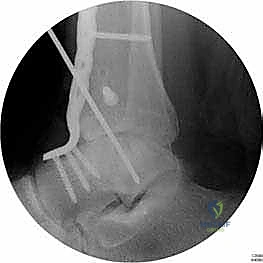

الخلاصة الطبية الشاملة: يُعد إجراء تثبيت مفصل الكاحل الأمامي (Anterior Ankle Arthrodesis) المعيار الذهبي والحل الجراحي الأكثر فاعلية لعلاج حالات خشونة الكاحل المزمنة والمتقدمة التي لم تعد تستجيب للعلاجات التحفظية. يهدف هذا التدخل الدقيق إلى إزالة الأنسجة الغضروفية التالفة ودمج عظام مفصل الكاحل (الظنبوب والكاحل) لتكوين كتلة عظمية واحدة صلبة ومستقرة. النتيجة المباشرة لهذا الإجراء هي القضاء التام على الألم المبرح واستعادة قدرة المريض على المشي وتحمل الوزن بثبات. يقدم الأستاذ الدكتور محمد هطيف، استشاري أول جراحة العظام والمفاصل وأستاذ جراحة العظام بجامعة صنعاء، هذا العلاج المتقدم بأعلى معايير الدقة العالمية، معتمداً على خبرة تتجاوز العشرين عاماً واستخدام أحدث تقنيات الجراحة الميكروسكوبية والمناظير، ليمنح المرضى فرصة حقيقية لاستعادة جودة حياتهم.

تثبيت مفصل الكاحل، أو "دمج الكاحل" (Ankle Fusion)، هو إجراء جراحي عالي التخصص يهدف إلى تحويل مفصل الكاحل المريض والمؤلم إلى كتلة عظمية واحدة صلبة وغير متحركة. الفلسفة الطبية وراء هذا الإجراء بسيطة وفعالة: "مفصل ثابت وبدون ألم أفضل بكثير من مفصل متحرك يسبب ألماً مبرحاً".

لماذا المدخل الأمامي (Anterior Approach)؟

تاريخياً، تم وصف العديد من المداخل الجراحية لتثبيت الكاحل (المدخل الجانبي، المدخل الخلفي، المدخل عبر المناظير). ومع ذلك، يُفضل الأستاذ الدكتور محمد هطيف استخدام المدخل الجراحي الأمامي في حالات محددة ولأسباب علمية قوية:

- رؤية ممتازة للمفصل: يوفر المدخل الأمامي رؤية بانورامية واسعة ومباشرة لكامل السطح المفصلي للظنبوب وعظم الكاحل، مما يسمح بإزالة الغضاريف التالفة بدقة متناهية.

- تصحيح التشوهات بدقة: يسمح هذا المدخل بتعديل انحرافات الكاحل (سواء كان يميل للداخل Varus أو للخارج Valgus) وإعادته إلى المحور الميكانيكي الطبيعي للساق.

- الحفاظ على عظم الشظية (Fibula): على عكس المدخل الجانبي الذي يتطلب غالباً قطع عظم الشظية، يحافظ المدخل الأمامي على الشظية سليمة، مما يحافظ على العرض الطبيعي للكاحل ويحمي الأربطة الجانبية.

- تثبيت ميكانيكي حيوي أقوى: يتيح المدخل الأمامي وضع شريحة معدنية (Anterior Plate) على الجانب الأمامي للمفصل. من الناحية الميكانيكية الحيوية (Biomechanics)، يعتبر الجانب الأمامي هو "جانب الشد" (Tension side) أثناء المشي. وضع الشريحة هنا يوفر تثبيتاً فائق القوة ويقلل من معدلات عدم الالتئام.